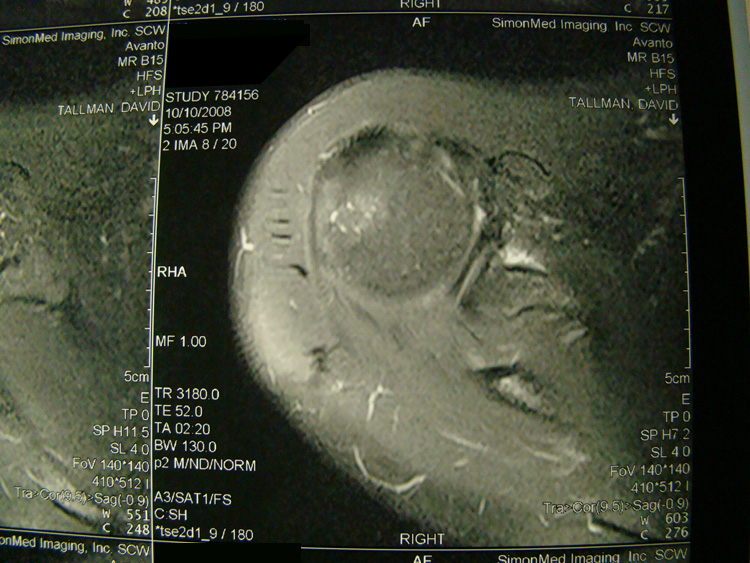

This patient presented with shoulder pain that interfered with work and exercise. The visible fluid-filled cysts on the “Before" MRIs are from chronically injured rotator cuff tendon roots.

The patient underwent treatments of a highly specialized fine-needling technique pioneered by Dr. Tallman.The follow-up MRI was done 2 months after his 6th treatment. He was released with a pain-free, full range of motion with unrestricted activities.